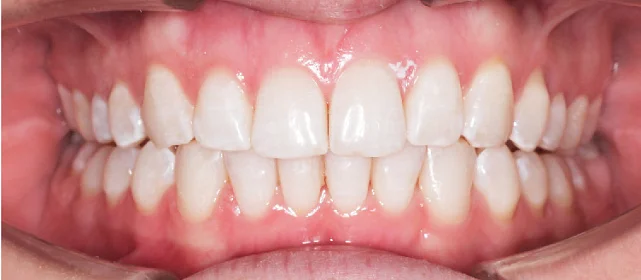

Результат

Зубы выровнены, скученность устранена, линия смыкания нормализована. Установлены несъёмные ретейнеры на обе челюсти, сняты слепки для ретенционных кап.

Решение: Поставили элайнеры Click на обе челюсти. Начали с 32 кап, но случай потребовал три дозаказа: 30, 10 и 10 кап — итого 82 капы за 30 месяцев. Количество дозаказов объясняется и сложностью случая (скученность плюс деформация кривой Шпее), и тем, что контрольные визиты были реже обычного из-за проживания за границей. Тем не менее результат достигнут: зубы ровные, смыкание в норме. На ретенцию пациентка приехала отдельно — зафиксировали ретейнеры на обе челюсти, сняли слепки для ретенционных кап.